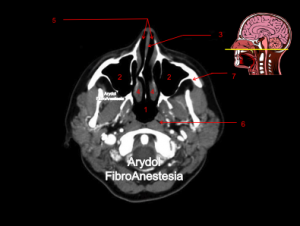

CORTE A NIVEL DE LA NASOFARINGE (CAVUM)

1.nasofaringe (cavum); 2. senos maxilares; 3. tabique nasal; 4. corenetes; 5.vía aérea fosas nasales; 6. trompa de Eustaquio; 7. rama mandibular